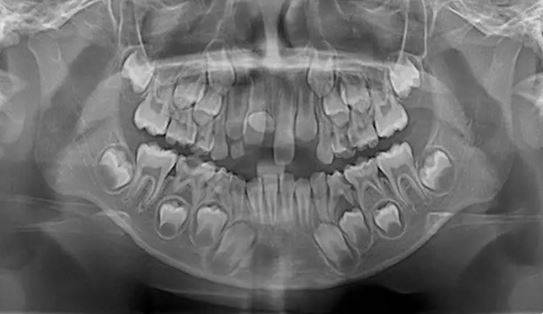

Röntgen Sonuçları Şaşırttı

Çekilen röntgen filmlerinde, çocuğun ağzında 18 süt dişi, 32 kalıcı diş ve bunlara ek olarak 31 adet “süpernümerer” olarak adlandırılan fazla diş bulunduğu ortaya çıktı. Yetişkinlerde normal kabul edilen 32 kalıcı diş sayısının çok üzerinde olan bu durumun, tıbbi literatürde istisnai vakalar arasında yer aldığı belirtildi.